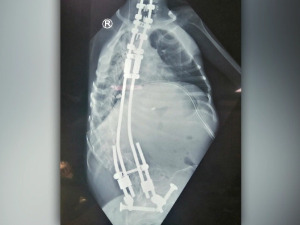

Сарадња са професором Вентуром донела је спас бројним пацијентима са најтежим деформитетима кичме

У протекле четири године, чувени шпански хирург професор Норберто Вентура са својим тимом, али и са нашим стручњацима, урадио је 112 хируршких захвата, чак 70 операција код деце са најтежим деформитетима...

Прочитај